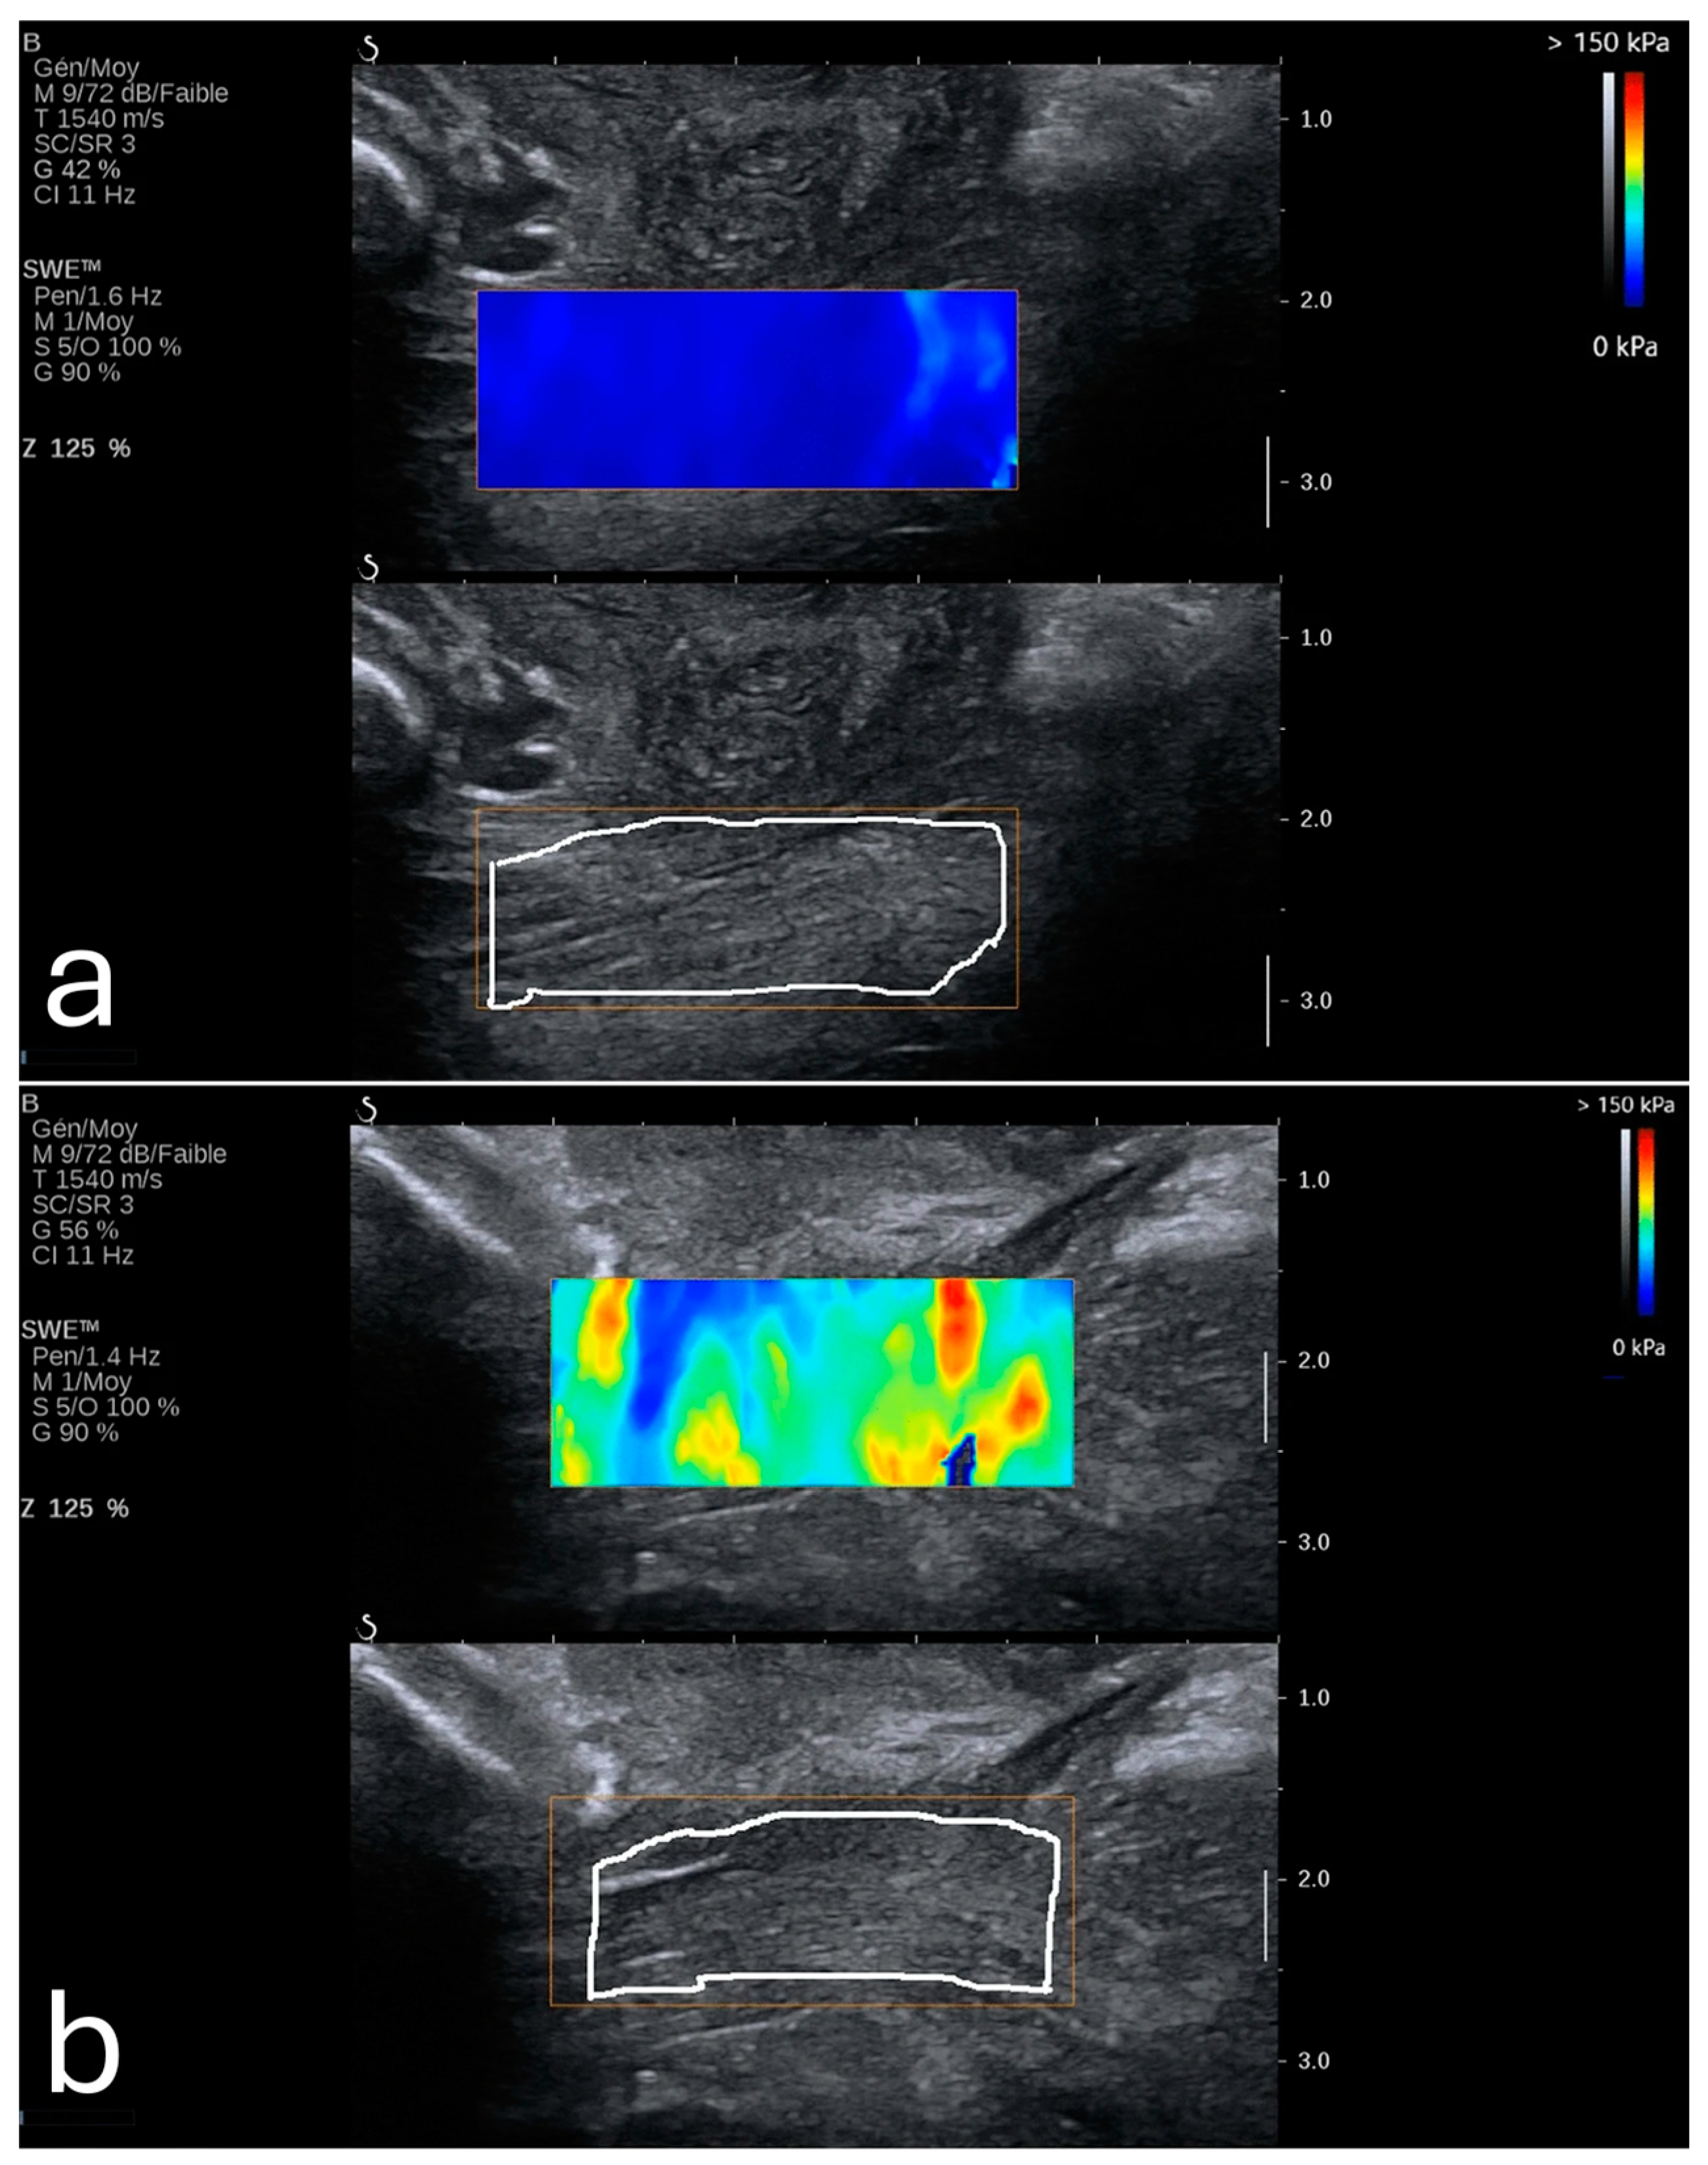

Furthermore, a 2024 study demonstrated that SWE could precisely measure tissue elasticity at specific cervical points, such as the inner and outer cervical os, yielding predictive values higher than cervical length alone []. When incorporated into a multifactorial model that included cervical length and pregnancy-related comorbidities, SWE achieved an AUC of 0.892, with a sensitivity of 86.7% and specificity of 79.2%. It also showed that SWE values were lower in PTB (8.76 kPa ± 3.04 kPa) in comparison to full-term pregnancies (14.95 kPa ± 8.21 kPa). These findings were most consistent when samples were taken from the anterior or posterior lip of the internal os, as illustrated in Figure 1. This combined approach shows promise for developing a more comprehensive PTB risk model that integrates both elastographic data and clinical factors [].

Figure 1. (a) Shear wave elastography image from a 26-year-old woman at 35 weeks gestation, showing high stiffness (11.1 kPa) in the anterior internal os; this patient delivered naturally at 38 + 4 weeks. (b) Shear wave elastography image from a 31-year-old woman at 34 weeks gestation, showing reduced stiffness (4.8 kPa) in the anterior internal os; this patient experienced preterm birth at 35 + 2 weeks due to premature rupture of membranes. Image adapted from Smith et al. [] under a Creative Commons Attribution 4.0 International License. Changes were made to resize and adjust the images.